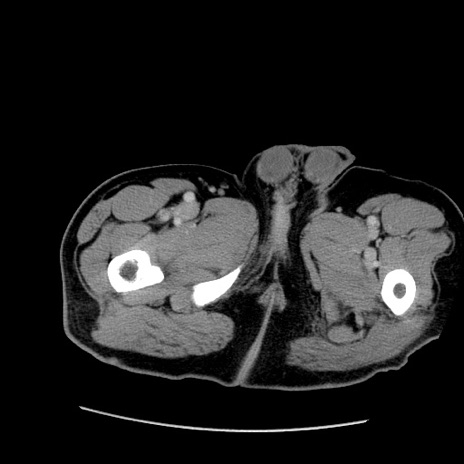

症例22(横断像)

【症例】50歳代男性

【主訴】腹痛

【現病歴】AVMからの被殻出血のため回復期リハ病棟入院中。 本日午後3時頃急に下腹部痛が出現した。

【既往歴】AVM、被殻出血、虫垂炎、高血圧

【身体所見】意識晴明、左半身不全麻痺、会話の理解は良好、36.5°C、腹部:膨隆、全体に板状硬、下腹部正中に圧痛点あり、反跳痛-、筋性防御不明、右下腹部にope scar

【データ】WBC 9400、CRP 0.06